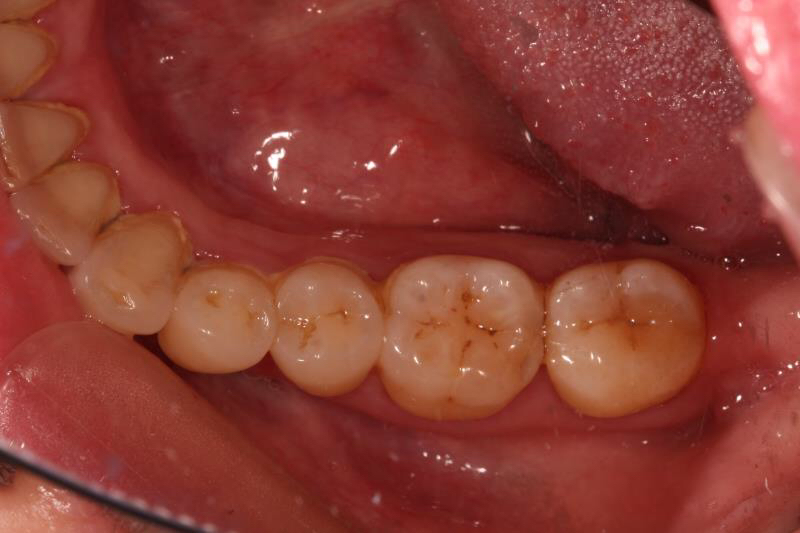

今天给大家分享的病例是一位中年女性,17缺失,由于长时间未修复,47伸长,留给17修复的空间不足。

老卢给她的治疗方案是:17种植修复,47根管治疗后截冠、高嵌体修复。这样可以最大限度的增加患者的咀嚼效率。

由于患者喉反射比较严重,种植牙冠和高嵌体都是用我们德国进口CEREC扫描制做的哦,与传统取模相比大大降低了不适感。